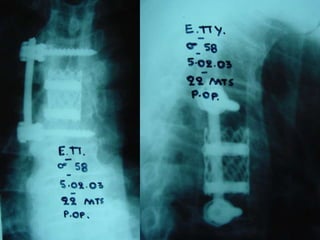

4th case

D.N.

M 61– Cardiologist

Symptoms

 Severe Neurologic deficit

 Intensive Thoracic-lumbar Pain

 High fever

Laboratory

 Neutroph. ↑

 SR 60

PMH

 Heavy smoker

 Diabetes melitus

 Recent Elbow Furuncle (untreated)

Follow up

Pus culture

(staphylococous aureous)

Antibiotics

 i-v for 2 mts

 orally for 7 mts

Complete neurologic recovery

4th case D.N. M 61–Cardiologist Symptoms  Severe Neurologic deficit  Intensive Thoracic-lumbar Pain  High fever Laboratory  Neutroph. ↑  SR 60 PMH  Heavy smoker  Diabetes melitus  Recent Elbow Furuncle (untreated)

Follow up Pus culture (staphylococousaureous) Antibiotics  i-v for 2 mts  orally for 7 mts Complete neurologic recovery